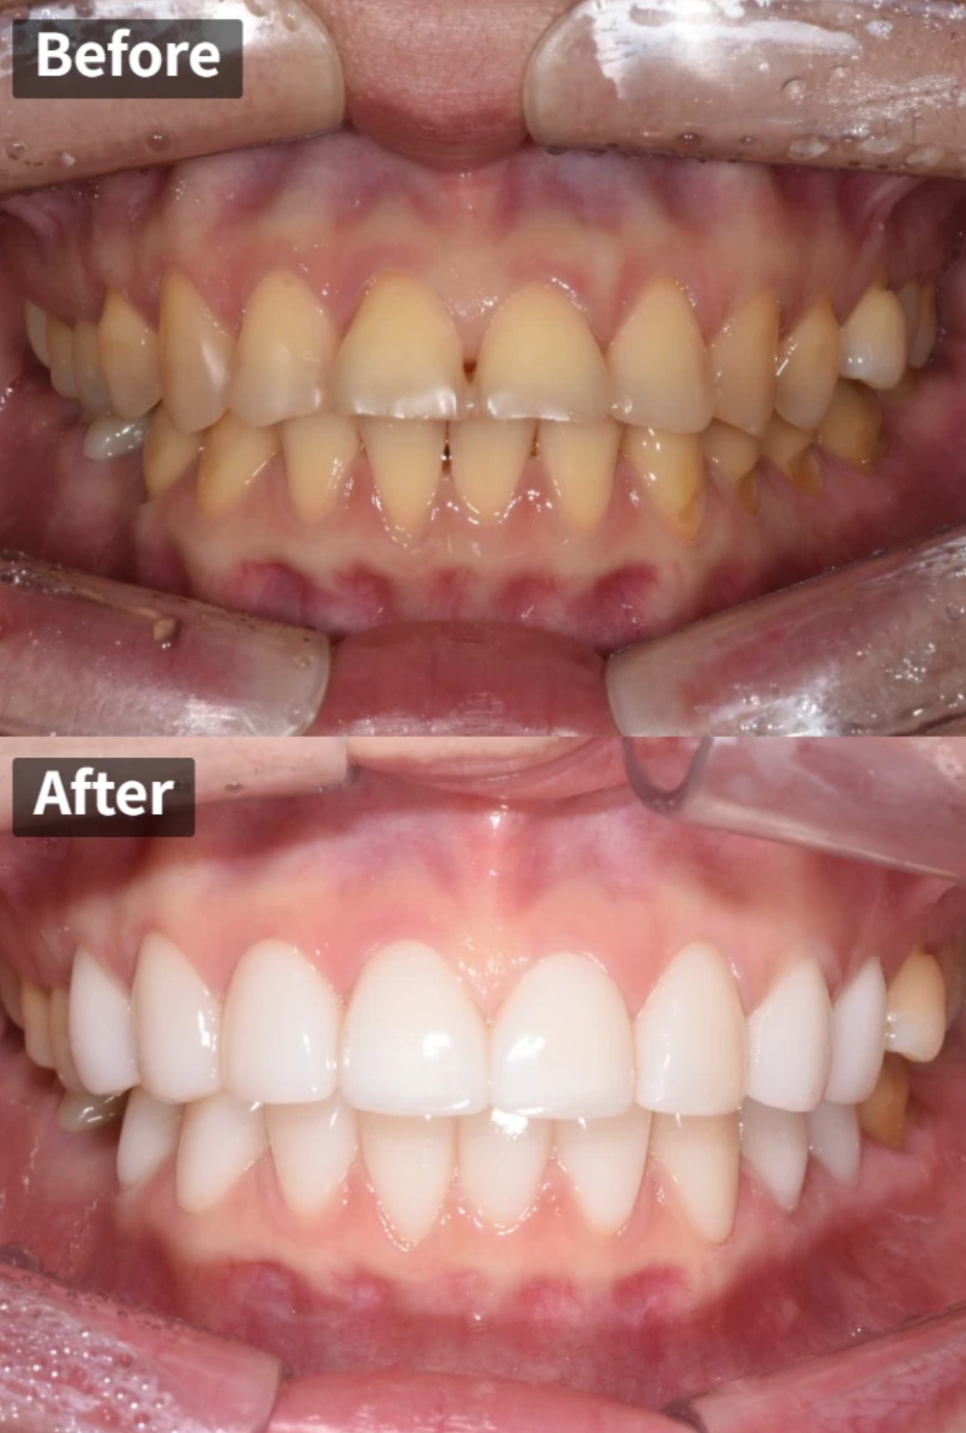

치료 결과 – Before & After

그럼 이제 가장 기다리셨을 치료 결과를 보여드리겠습니다.

윗니 결과

밝고 균일한 색상, 자연스러운 형태, 환자분 희망 스타일과 거의 일치함

윗니는 정말 극적인 변화를 보여줍니다. 누렇던 색상이 밝고 균일한 톤으로 개선되었고, 레진 수복 흔적은 완전히 사라졌습니다. 돌출되었던 가운데 앞니 두 개는 자연스럽게 정렬되었고, 치아 사이에 있던 검은 삼각형도 깔끔하게 폐쇄되었습니다.

특히 잇몸성형을 병행한 덕분에 잇몸 라인도 고르게 정리되어 전체적으로 훨씬 조화로운 모습이 되었습니다. 환자분이 처음에 보여주셨던 레퍼런스 사진의 스타일과 거의 일치하는 결과물이 완성되었습니다.

아랫니 결과

치료 후 아랫니

아랫니도 마찬가지로 큰 변화가 있었습니다. 삐뚤어져 있던 앞니가 가지런하게 정렬되었고, 가운데 앞니 사이 벌어져 있던 공간도 자연스럽게 메워졌습니다. 잇몸 경계가 마모되어 있던 부위도 세라믹 레진필링으로 깔끔하게 수복되었습니다.

치료 전과 비교하면 색상, 형태, 잇몸 라인 모두 극적으로 개선된 것을 확인하실 수 있습니다.